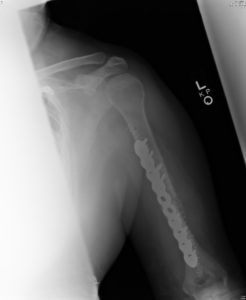

Fractures to the mid portion (shaft) of the upper arm (humerus) are not as common as fractures to the shoulder region. The humeral shaft is cylindrical in shape and serves as a point of attachment for several muscles that aid in movement of the shoulder and elbow. The radial nerve travels intimately close to the humeral shaft and fractures in this area can cause injury to the nerve. Damage to the radial nerve in this region can cause an inability to extend the wrist and fingers.

Humeral shaft fractures can be treated with bracing in many circumstances. The brace will help to hold fracture alignment while allowing function of the arm to resume. When alignment cannot be adequately held by the brace, or when a faster return to weight bearing on the arm is necessary, surgery may be performed. Surgery typically entails placing a plate and screws or a rod and screws to fix the fracture. Healing time and return to full activity are often less with surgery than with nonsurgical treatment.